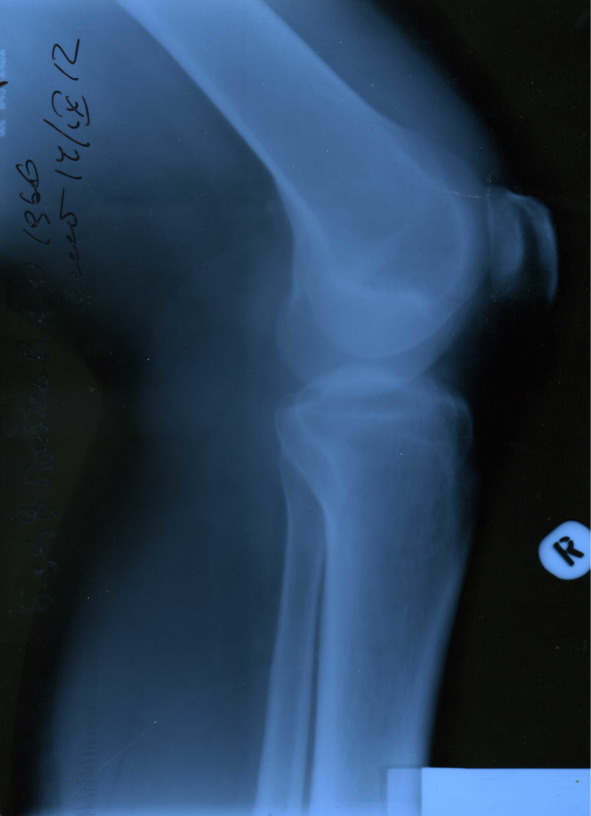

В сентябре 2012 года, когда уже оба сустава по кругу обострялись ни один раз, в очередной раз случилось обострение, и я все-таки решил обратиться к коллеге-хирургу за обследованием и профессиональной помощью. После общего осмотра было назначено рентген-обследование коленных суставов (все снимки представлены ниже).

Изменения малозаметны, но все же диагноз хронический остеоартроз подтвердил врач-рентгенолог, хирургом назначены обезболивающие средства и аппликации сустава димексидом.

Итак. Мы вместе со старшим сыном делали рентгенологическое исследование суставов и кровь на боррелиоз сдали одновременно.

Анализ ИФА ничего не выявил ни у меня, ни у сына. Кстати, на рентгене у моего старшего рентгенолог описал какую-то врожденную аномалию крестообразной связки. Но этот дефект его никогда больше не беспокоил. Здесь также можно усмотреть связь с питьевой водой, ведь фильтр для воды стоял у меня дома, и все члены моей семьи пили эту воду, может быть на так фанатично, как я.